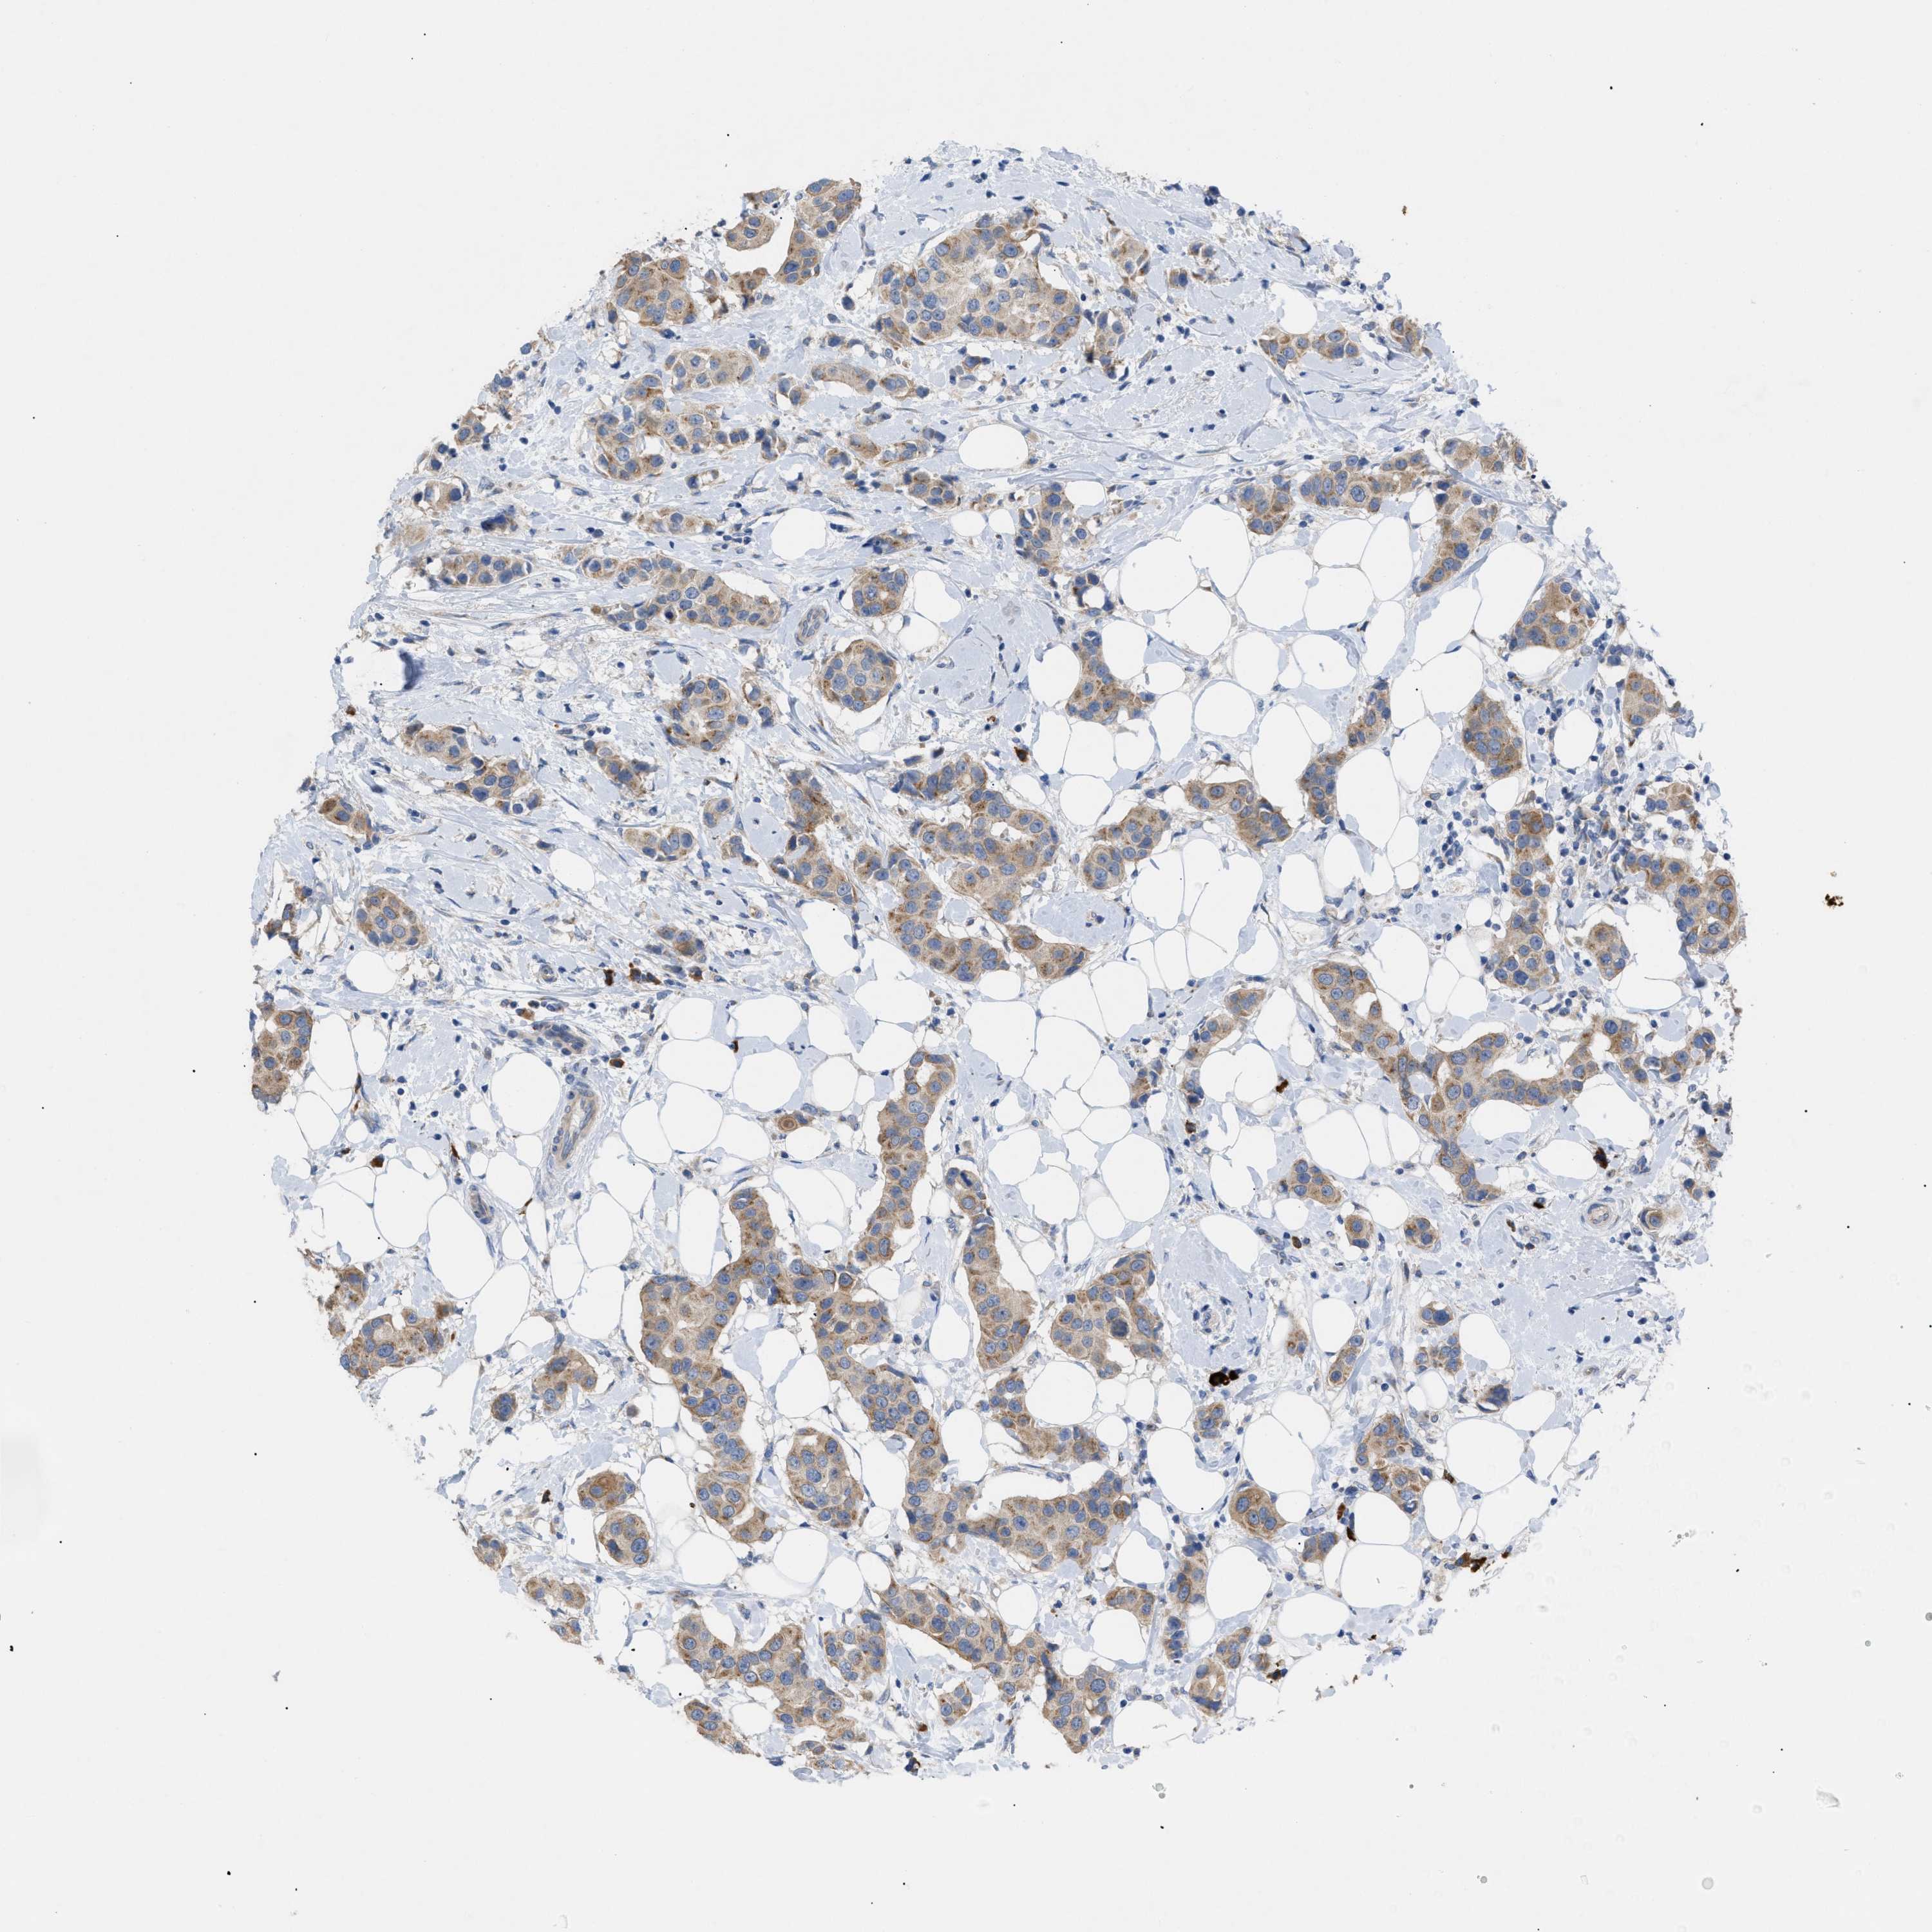

CANCER BREAST CANCER Show tissue menu

BRCA TCGA BRCA VALIDATION PROTEIN EXPRESSION